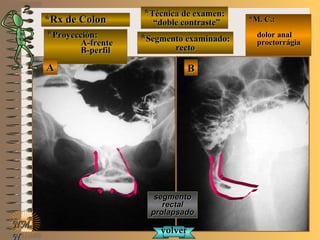

a ver lasa ver las

imágenesimágenes

En estas radiografías en proyección de frente seEn estas radiografías en proyección de frente se

deben distinguir los distintos segmentos gástricos,deben distinguir los distintos segmentos gástricos,

la distribución de los pliegues y la presencia dela distribución de los pliegues y la presencia de

áreas gástricas que nos permiten aseverar que laáreas gástricas que nos permiten aseverar que la

mucosa del estómago esta indemnemucosa del estómago esta indemne

**Opción avanzada para volver a ver las imágenes con reparosOpción avanzada para volver a ver las imágenes con reparos

NMNM

D. F. M.D. F. M.

UNTUNT

E ME M

*Rx de Estómago*Rx de Estómago

**Proyección: frenteProyección: frente

**Técnica de examen:Técnica de examen:

A-“relleno total”A-“relleno total”

B- “mucosografía”B- “mucosografía”

C- “doble contraste”C- “doble contraste”

**Segmento examinado:Segmento examinado: